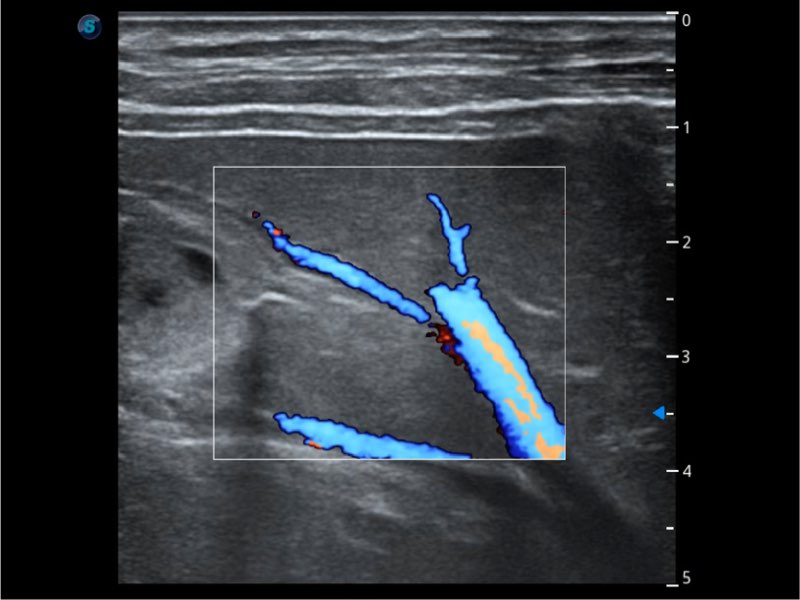

Przy pracach nad aparatem ProPet 60 uwzględniono najważniejsze preferencje i potrzeby weterynarzy, oferując finalnie przystępne cenowo i odpowiednio wyważone połączenie znakomitej precyzji klinicznej, zwiększonej wydajności i przemyślanego przebiegu pracy, niezastąpione w codziennej praktyce weterynaryjnej. Dzięki dostępowi do pełnej gamy głowic HD rozwiązanie to spełnia wszystkie potrzeby w zakresie obrazowania, umożliwiając wykonywanie badań jamy brzusznej, małych narządów, ortopedycznych, badań podczas rozrodu, a nawet badań serca i klatki piersiowej, a to wszystko przy doskonałym stosunku jakości do ceny.